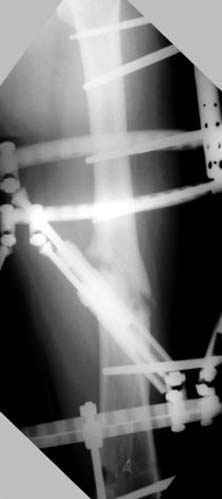

Несколько снимков из моей коллекции, чтобы разьяснить, почему мы до сих пор делаем различные варианты остеотомии.

На рисунке N1 предоперационный план лечения ложного сустава шейки бедра- линия ложного сустава, угол и направление введения импланта, клиновидная остеотомия в градусах и миллиметрах, второй снимок после коррекции, расчет, на сколько удлиняется конечность и размеры импланта;

N3 рисунок окончательный снимок, после операции моя рентгенограмма должен выглядеть примерно как эта картина. На N4 снимке клин перед удалением; N5 послеоперации 3 нед.; N6 окончательная рентгенограмма.

(доложен в Ст. Петербурге 2003 и в Москве 2004)

варус при проксимальном отделе 95 градусной пластиной.

пластическая модель; и коррекция бедра аппаратом Илизарова.

Имею другие снимки тоже, получится как отчет о моей работе.